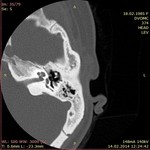

Строение сосцевидного отростка различается в зависимости от количества воздухоносных полостей в нем, их величины и расположения. Формирование этих полостей происходит путем замещения костно-мозговой ткани врастающим мукопериостом. По мере роста кости количество сообщающихся с пещерой воздухоносных ячеек все время увеличивается. По характеру пневматизации различают пневматический, диплоэтический и склеротическийтипы строения сосцевидного отростка (рис. 5.9).

Рис. 5.У.Типы строения сосцевидного отростка:

а - пневматический; б - диплоэтический; в - склеротический

При пневматическомтипе строения воздухоносные ячейки заполняют почти весь отросток и распространяются иногда даже на чешую височной кости, скуловой отросток, пирамиду. Обычно около пещеры образуется зона более мелких клеток, к периферии они становятся все более крупными, нередко при этом имеется большая верхушечная клетка.

Диплоэтический(спонгиозный, губчатый) тип строения характеризуется небольшим количеством воздухоносных клеток. Они располагаются преимущественно вокруг пещеры и представляют собой небольшие полости, ограниченные трабекулами.

Склеротический(компактный) тип строения отростка является следствием нарушения обменных процессов или результатом перенесенных общих или местных воспалительных заболеваний. При этом сосцевидный отросток образован плотной костной тканью с отсутствием ячеек или их минимальным количеством.